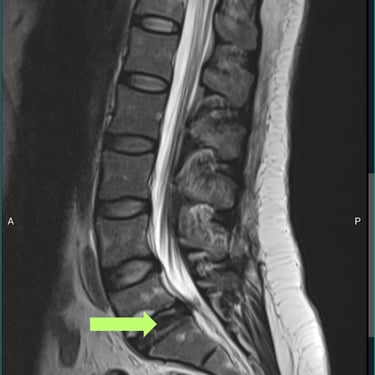

🧠 Listesis L4–L5 con Estenosis Severa: Estabilización con Fijación Transpedicular (FTP) y Fusión Intersomática Transforaminal (TLIF)

La listesis L4–L5 con estenosis severa provoca dolor lumbar e inestabilidad con compresión nerviosa. La fijación transpedicular (FTP) y la fusión intersomática transforaminal (TLIF) permiten descomprimir el canal espinal, estabilizar la columna y mejorar la función de forma segura y progresiva.